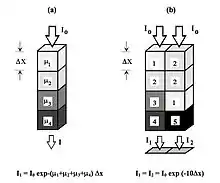

Image Reconstruction Basics

- A cross-sectional layer called a tomographic slice of the body is obtained by dividing it into many tiny volume elements called voxels - see Figure 7.10. When displayed on a computer screen, each voxel is represented in two dimensions by a pixel. The task in CT is to assign a number to each voxel that is proportional to its X-ray attenuation. This can be achieved by rotating an XRT and an array of detectors around the slice of interest to measure the radiation intensities projected at different angles around that slice. In other words, multiple views around the slice are acquired. An image reconstruction algorithm is then applied to this projection data to estimate the attenuation in each voxel. The amount of attenuation for a voxel is determined by its composition and size, along with the X-ray energy, and is characterised by a parameter (which can be expressed in Hounsfield Units, HU) derived from the linear attenuation coefficient, μ.

- A basic premise in back-projection is that any attenuation of the X-ray beam has occurred uniformly along the path followed from the source to the detector. Let's consider a simple tomographic slice containing just four voxels to illustrate the computational approach - see Figure 7.11. The first projection, P1 is obtained from a horizontal exposure from left to right in the figure. The back-projection of P1 involves putting the values 7 and 9 in both elements of the first and second rows, respectively. The second projection, P2 adds a 4 to the top right element, 1 to the bottom left element and 11 to the other two elements when it is back-projected. The other projections are treated in a similar fashion. Following regularisation of the data set the final image is obtained at the bottom left of the figure.